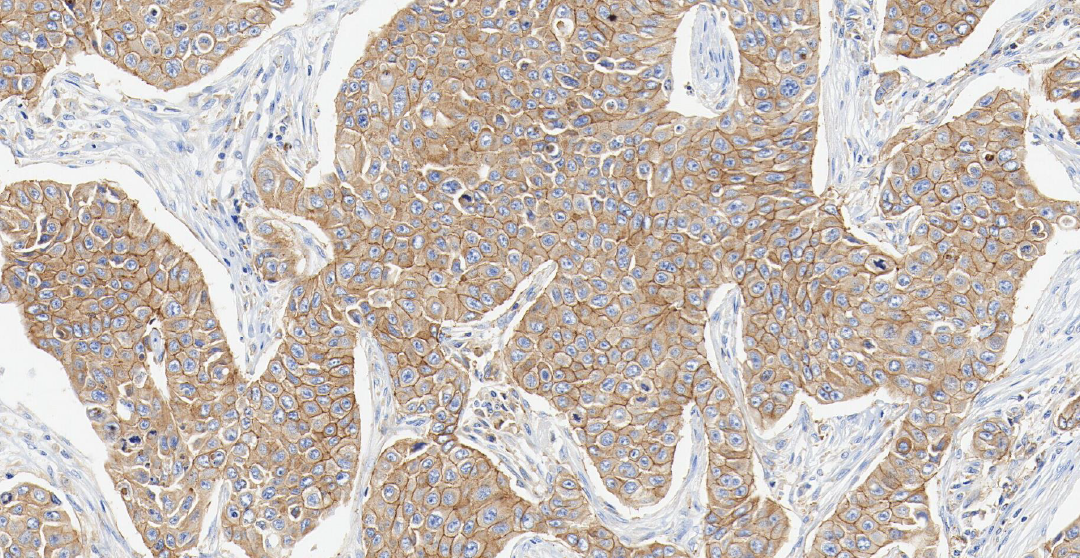

MET

MET ——MET 基因是定位在人类第 7 号染色体上的一个原癌基因,其编码生成的 c-Met 蛋白属于受体酪氨酸激酶家族。

定位: 细胞膜。

功能: MET 是肝细胞生长因子 (HGF) 的受体。正常的 HGF/MET 信号通路精密调控胚胎发育、组织再生和损伤修复过程中的细胞增殖、分化和迁移。

在肺癌中,MET 可通过基因扩增、蛋白过表达或 14 号外显子 (METex14) 跳跃突变等方式异常激活,导致下游促生长和生存信号通路持续活化,驱动肺癌的生长、存活和转移。 MET 扩增/过表达是 EGFR 靶向治疗获得性耐药的重要机制之一 [6] 。

图 3.人肺癌组织的 MET 免疫组化分析 (HY-P86238)。